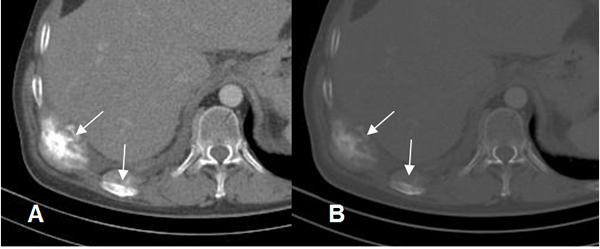

Fig 45. Metástasis blásticas.

A: TAC en ventana de tejido y B: en ventana ósea. Lesiones expansivas en los arcos costales posteriores, de características blásticas, que corresponden a metástasis por neoplasia de mama.